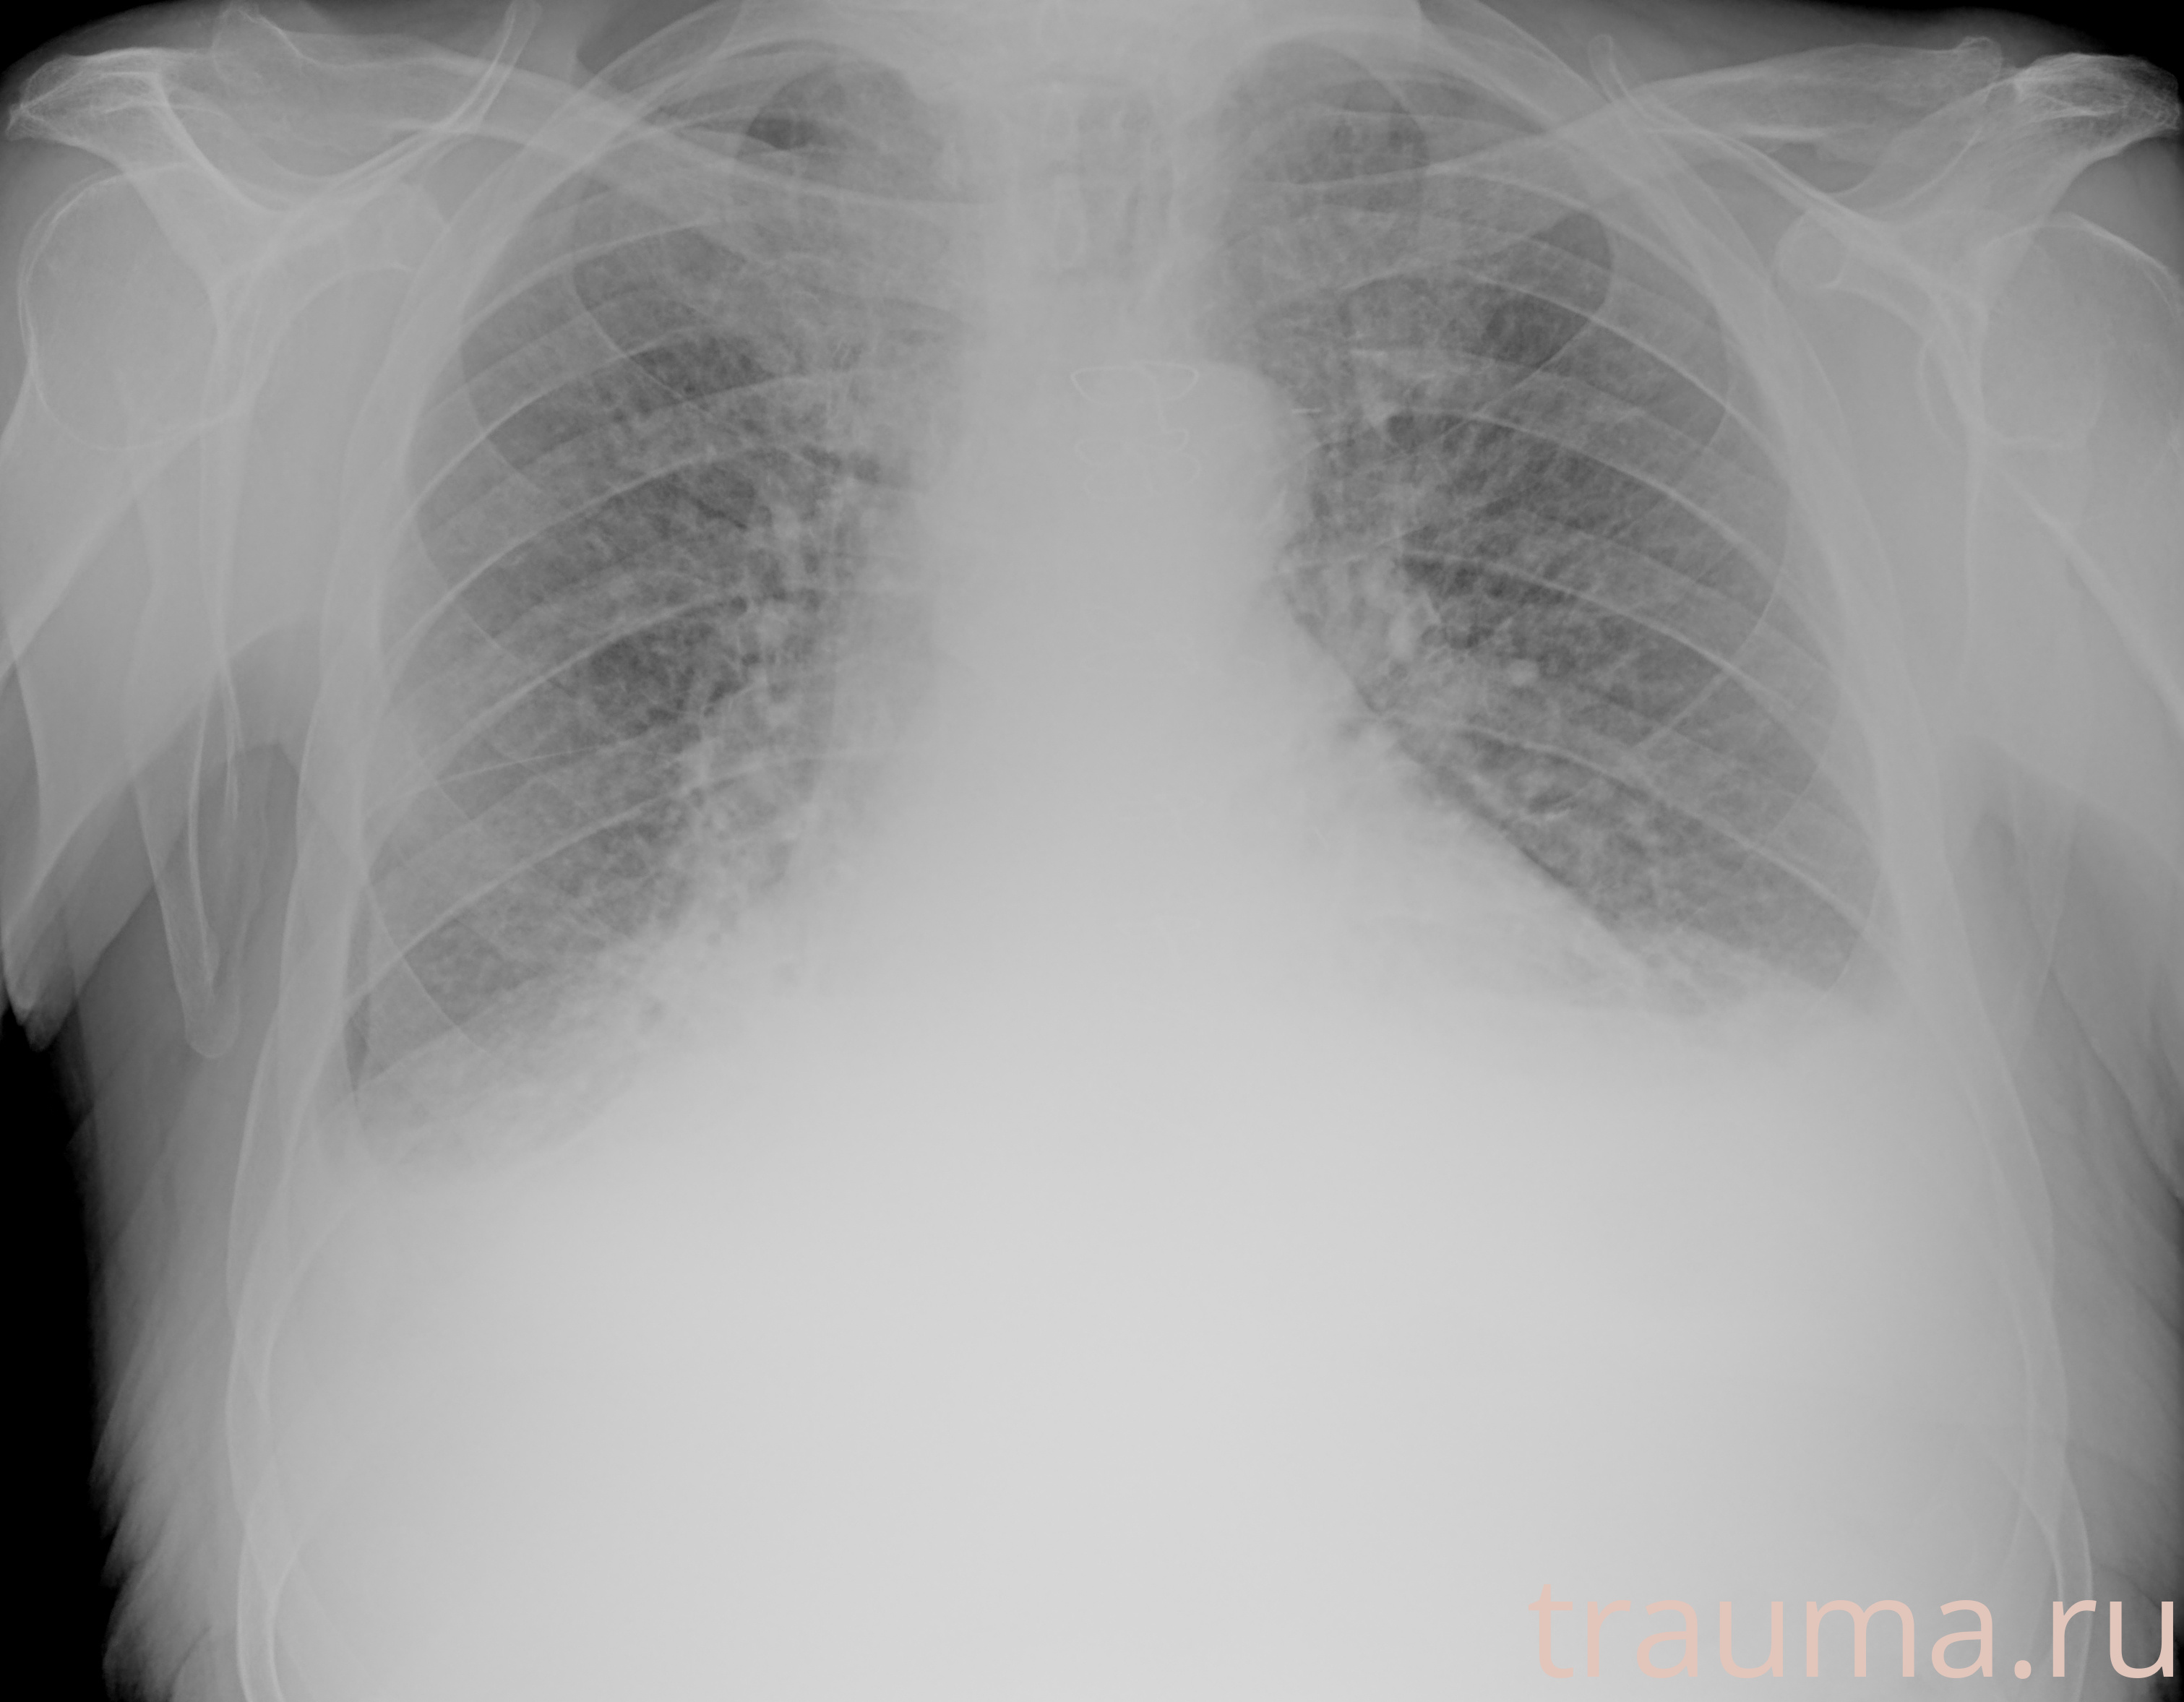

Рентген на дому: по вашему адресу приезжает врач-рентгенолог, травматолог-ортопед с мобильным рентгеновским аппаратом, проводит диагностику травмы или заболевания, делает необходимые рентгенограммы, дает рекомендации по дальнейшему лечению. Получить качественные снимки в домашних условиях возможно благодаря уникальной методике, разработанной МосРентген Центром для института  Склифосовского